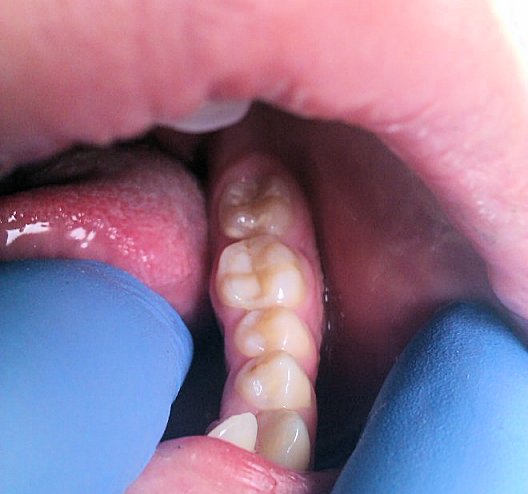

This is an alternative to gold or all ceramic inlays. The material is a composite resin which is white in appearance and enables inlay/onlay to match the rest of your teeth.

Composites are a good choice for people with tooth decay which is too far advanced for a filling but not serious enough for a crown.

A composite inlay creates a very natural looking appearance. They provide a water tight seal between the tooth and composite which prevents the risk of bacteria entering the gap and causing infection.